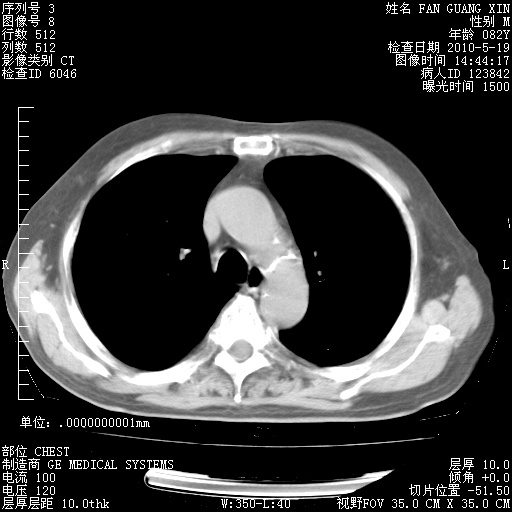

复查肺部CT,明显好转。为什么发热呢?

治疗3周后的肺部CT

治疗3周后的肺部CT纵隔窗